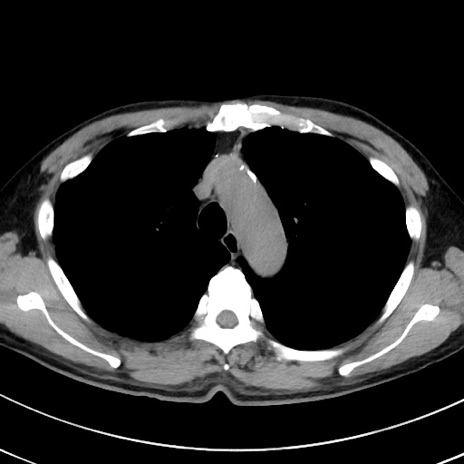

冠状断像